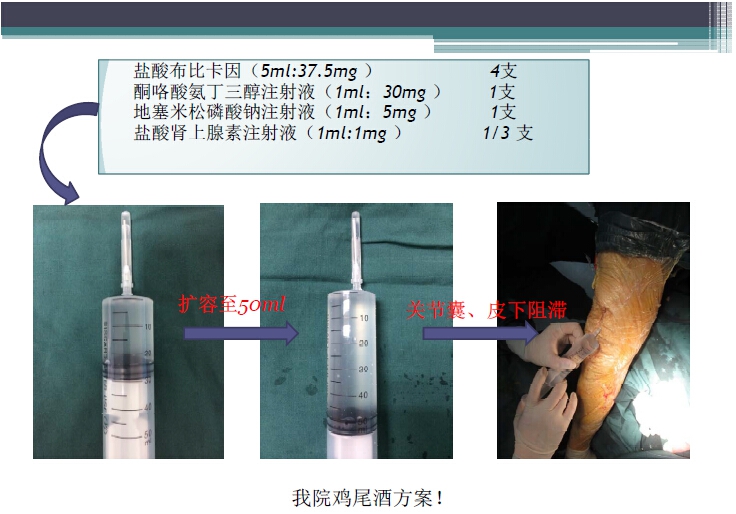

对于关节外科而言快速康复实际上是以病人加速舒适康复为目的,加强围术期的综合管理,包括疼痛和睡眠管理、血栓预防管理、感染预防管理、围术期血液管理,减少放置引流管、尿管、减少止血带应用,减少术后恶心呕吐,尽早进食,尽早康复等,逐步达到无血、无痛、无栓、无感、无肿、无管、无吐、无带等优良效果。为此,小编特邀王坤正教授等多位关节外科的专家参与撰写快速康复外科在关节外科的应用的主题文章,共话“人工关节置换快速康复”新理念,探讨建立符合我国特色的关节置换围手术期管理与快速康复体系,促进我国关节外科技术整体发展与提高。